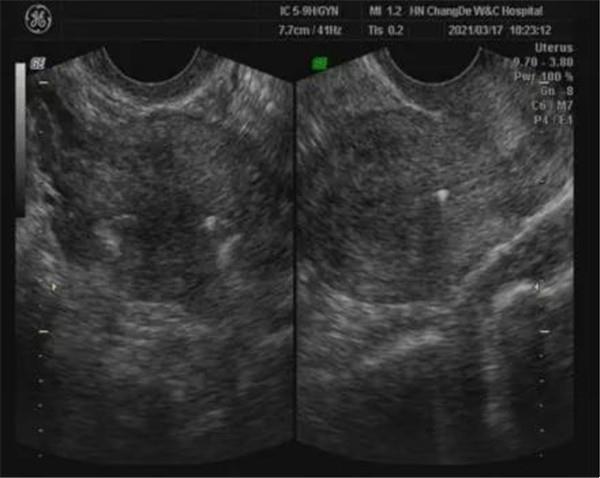

患者劉某,上環(huán)后半年一直有小肚子隱隱痛,看了兩家醫(yī)院,檢查都沒有問題,月經(jīng)期消炎2個月了,還是不好,上月到我院做一個精準(zhǔn)婦科超聲,我院影像科醫(yī)生仔細(xì)檢查并進(jìn)行宮腔三維成像,發(fā)現(xiàn)環(huán)確實好好的呆在宮腔,但順時針旋轉(zhuǎn)了95℃(如下圖),于是臨床醫(yī)生將環(huán)處理,上周回訪患者下腹隱隱痛的感覺消失了。

節(jié)育器的主要臨床作用就是避孕(部分激素環(huán)有治療作用)。那么超聲檢查節(jié)育器,最主要目的是明確節(jié)育器的位置,有無異位,嵌頓,同時對于放置宮內(nèi)節(jié)育器后,患者出現(xiàn)的各種臨床不適,二維超聲未提示明顯異常,但三維超聲提示節(jié)育器旋轉(zhuǎn),所以不適癥狀可能與節(jié)育器宮內(nèi)旋轉(zhuǎn)有關(guān),臨床換環(huán)后,患者癥狀能消失。